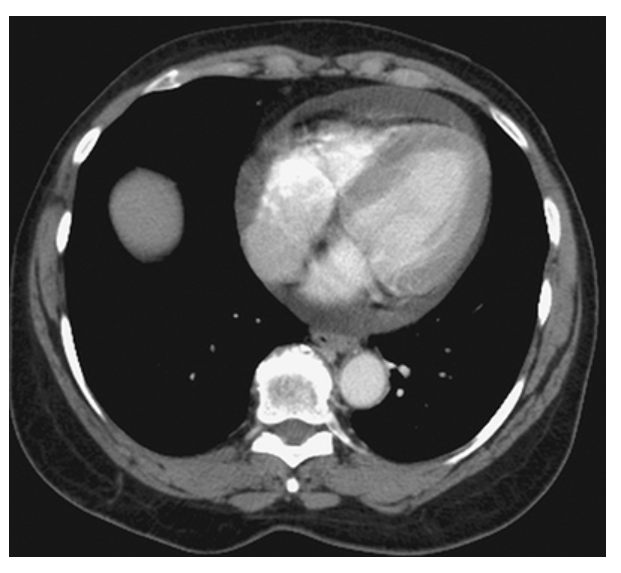

Pericardial Effusion. Contrast-enhanced CT (CECT) shows increased fluid density around the heart consistent with a pericardial effusion.

Pericardial Effusion. Normal for comparison.